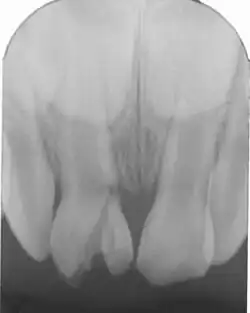

Kronenfraktur mit gut erkennbarer Pulpaeröffnung an Zahn 11. 16-jähriger Patient, -

Röntgenbild (Zahnfilm) des frakturierten Zahnes -